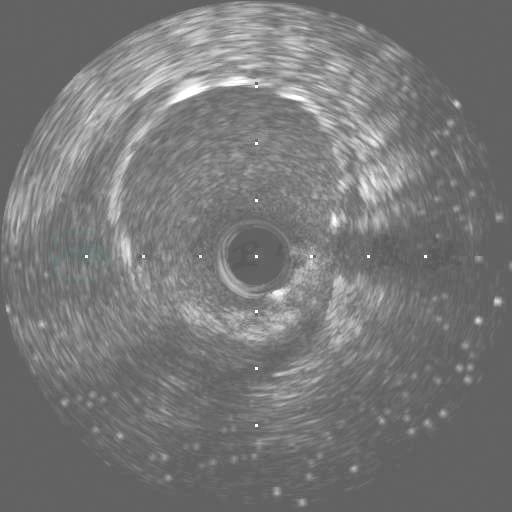

图28 LAD血运重建后复查IVUS:支架术后支架远端外,LAD中段支架未覆盖的部分冠脉仍然存在偏心的动脉粥样硬化斑块

图29 LAD血运重建后复查IVUS:支架远端,支架扩张良好

图30 LAD血运重建后复查IVUS:支架中段,支架扩张良好

图31 LAD血运重建后复查IVUS:支架近段,支架扩张良好

图32 LAD血运重建后复查IVUS:支架近段没有覆盖LCX开口

图33 LAD血运重建后复查IVUS:支架没有累及LM